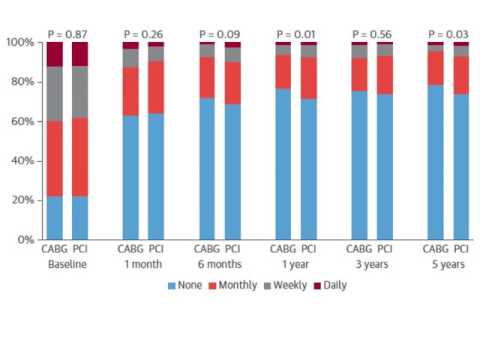

10 años de resultados de stent vs bypass a TCI. Dr. Gerardo Albarracín. Residencia de Cardiología. Hospital C. Argerich. Buenos Aires